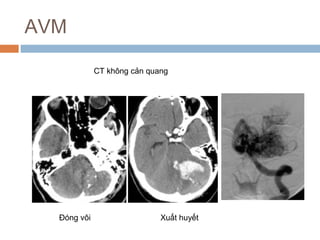

CT không cản quang

AVM: hình ảnh CT

 Xuất huyết

 Đóng vôi: 25-30%

 Bắt quang

 CTA: Dãn động mạch

và tĩnh mạch dẫn lưu

Đóng vôi Xuất huyết